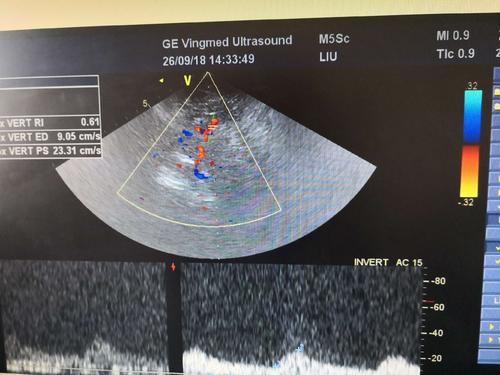

經顱彩色編碼雙功能超聲TCCD成像模式分析

經顱彩色編碼雙功能超聲,區別于經顱多普勒超聲,它的英文簡稱是TCCD,后者是TCD。TCCD成像模式是什么樣的,tcd廠家澳思泰今天來分析這一問題。

(1)依據多普勒頻移值編碼成像即f-TCCD:

依賴運動紅細胞所產生的多普勒頻移值進行計算機編碼,可以顯示血流方向和測算血流速度,需要校正多普勒取樣角度,角度及篩查深度依賴性較大,較易產生運動偽像。

(2)依據運動紅細胞所產生的總能量進行編碼成像即p-TCCD:

只與運動紅細胞所產生的總能量有關,無需校正多普勒取樣角度,對于受取樣角度影響較大血管病變,諸如大腦后動脈(PCA),大腦中動脈(MCA)M2段,大腦前動脈(ACA)A1段有一定的幫助作用,信噪比更高,不易產生混疊效應。p-TCCD相對f-TCCD而言,缺點是不能顯示血流方向,對顯示狹窄處高速血流敏感性較低。